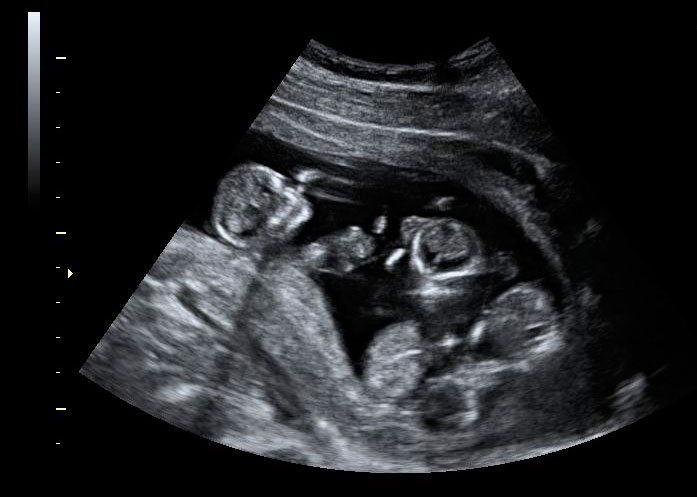

En la imagen podemos ver un feto de 12 semanas en una ecografía tridimensional. Se pueden observar con nitidez el cordón umbilical y las paredes uterinas. También, las estructuras básicas del bebé como cabeza, tronco y extremidades. A estas alturas de gestación, el niño presenta un aspecto muy parecido al de un recién nacido, a falta de la maduración completa de sus órganos.

Ecografía 3D: Feto de perfil de 12 semanas